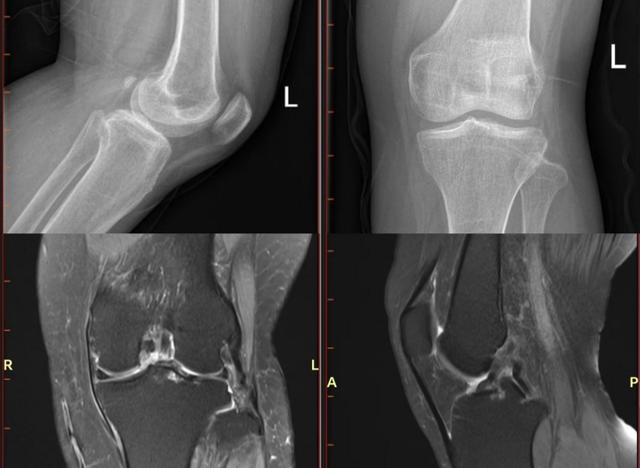

关节骨科主任骆阳经过仔细体查,发现刘女士的左膝关节呈现出轻微的肿胀迹象,特别是在膝关节的内侧和外侧间隙处,即便是轻轻的按压,也会引发明显的疼痛反应。进一步专科检查结果显示,十年前那一摔刘女士膝关节后交叉韧带、后外侧结构损伤,由于多年未得到妥善治疗,左膝关节软骨已经退变,影响了关节的正常功能。

在充分了解了手术方案和预期效果后,家属和患者同意进行手术。手术当天,骆阳主任带领团队凭借精湛的技术和默契的配合,成功完成了LARS人工韧带重建膝关节后交叉韧带+后外侧复合体重建手术。术后,在医护人员的悉心照料下,刘女士恢复良好。